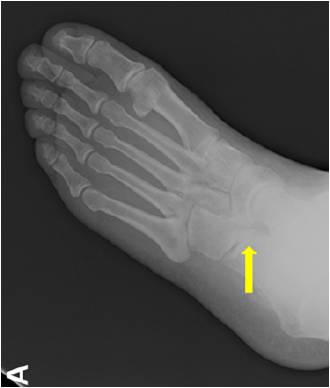

放射学特征:跟距联合在侧位X线片上呈现C sign,跟舟联合在侧位X线片上呈现食蚁兽鼻征 拍摄45°内斜位X片观察跟舟联合。跟骨轴位(Harris and beath): 跟骨轴位X线片观察跟距联合。